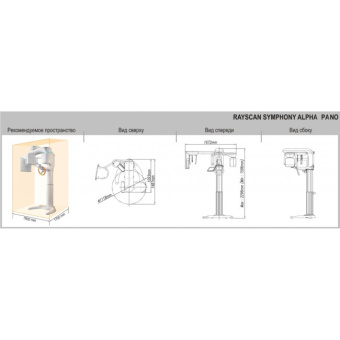

Rayscan a-SC (Alpha Pano Ceph) – панорамный рентгеновский аппарат последнего поколения с цефалостатом. Аппарат предназначен для панорамного сканирования зубов, челюстей и полости рта, а также включает в себя функцию сканирования для получения изображения головы. Специально разработанная конструкция аппарата позволяет в дальнейшем вне заводских условий произвести его дооснащение функцией компьютерной томографии (КТ). В стоимость аппарата входит мощный компьютер, программное обеспечение и беспроводной RF-пульт управления.

- Возможность дооснащения ортопантомографа с цефалостатом компьютерным томографом (далее КТ). В специальной конструкции аппарата предусмотрены технические возможности, позволяющие в дальнейшем ортопантомограф вне заводских условий дооснастить функцией КТ. Такой аппарат очень рациональное приобретение с поэтапным вложением средств. Ортопантомограф Alpha имеет компактный ультрасовременный дизайн, аппарат не только эффектно выглядит, но и занимает мало места в помещении.